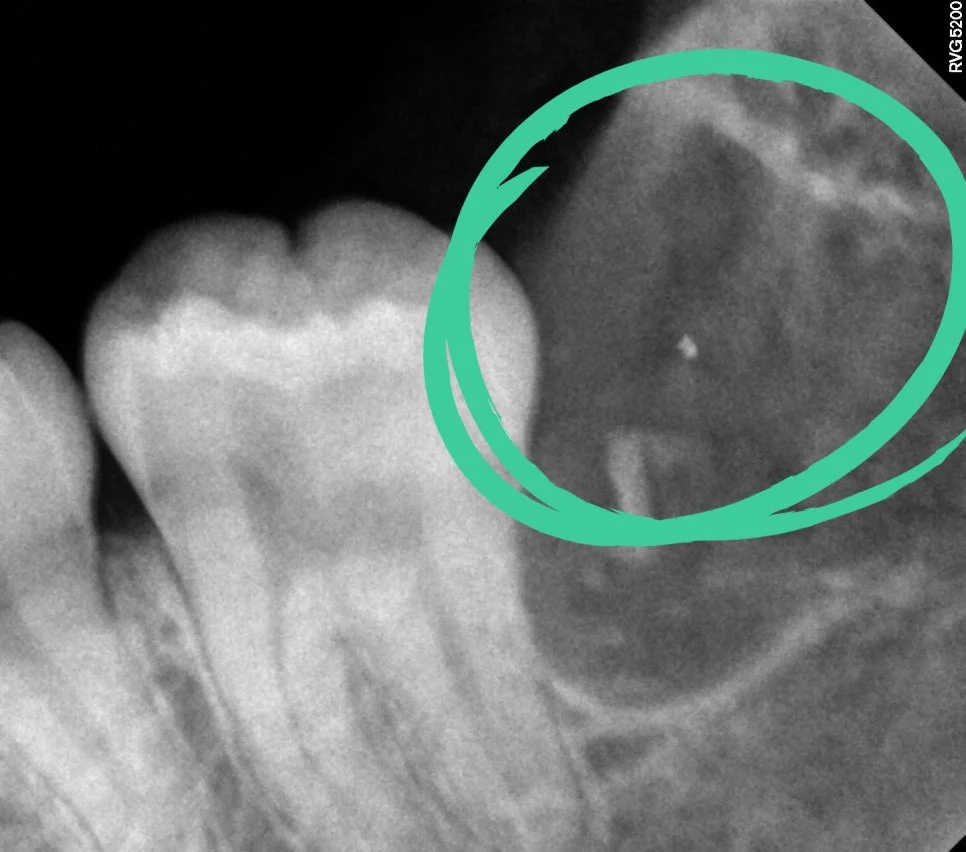

좌측 매복 사랑니 진단

매복 사랑니 좌측 치근단 X-ray

좌측 치근단 X-ray

제2대구치와 사이 관리가 어려운 좌측 하악 매복 사랑니입니다. 살짝 맹출된 상태이지만 관리가 되지 않아 발치가 필요한 상태입니다.